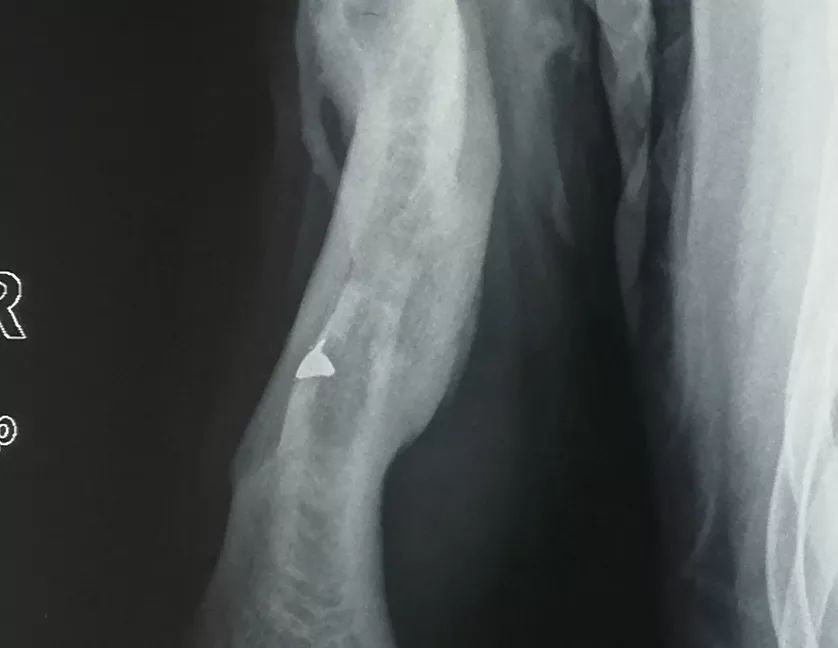

右上臂內(nèi)的彈片X光圖

原來老郭是一名越戰(zhàn)老兵,曾經(jīng)參加過1979年對(duì)越自衛(wèi)反擊戰(zhàn),他右臂上的傷,也是那時(shí)候留下的。1979年2月17日,對(duì)越自衛(wèi)反擊戰(zhàn)正式打響,當(dāng)兵三年的老郭跟隨部隊(duì)開赴中越邊境,身為偵察兵的他,很快就與戰(zhàn)友進(jìn)入前線。在諒山25號(hào)高地與敵人的一場(chǎng)遭遇戰(zhàn)中,老郭所在的偵察排35名戰(zhàn)士陣亡27人,他也在這場(chǎng)戰(zhàn)斗中右臂中彈。轉(zhuǎn)往戰(zhàn)地醫(yī)院后,經(jīng)過手術(shù)取出了他右臂內(nèi)的彈頭,但由于當(dāng)時(shí)的醫(yī)療條件限制,殘留在傷口內(nèi)的碎彈片并未被發(fā)現(xiàn)。

殘留的彈片像老友一樣陪伴老郭走過了四十年的風(fēng)風(fēng)雨雨,但也時(shí)不時(shí)的通過引發(fā)傷口的疼痛提醒老郭它的存在。在瑞慈醫(yī)院檢查發(fā)現(xiàn)殘留的彈片后,骨科王瑞良主任立刻就為老郭安排了手術(shù)。